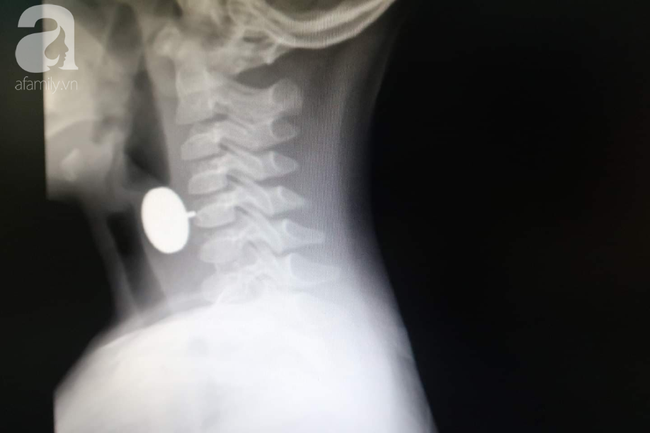

Dị vật nhìn qua hình chụp X-quang. (Ảnh: BVCC)

Ngay lập tức người nhà đưa bé vào cấp cứu. Sau khi thực hiện các cận lâm sàng cần thiết, các bác sĩ xác định có dị vật mắc ở vị trí vùng cổ của bé.

Ngay lập tức, bé được thực hiện nội soi cấp cứu có tiền mê. Các bác sĩ nhanh chóng kiểm tra thấy dị vật là kim loại hình tròn đường kính 20 mm, ở giữa có trục và kim loại nhô ra ngoài sắc nhọn cắm vào 1/3 thực quản trên của bé trai.